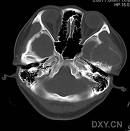

顱骨嗜酸性肉芽腫:嗜酸性肉芽腫是一種良性病變,多見於兒童和青年,也可見於其他年齡。男性多於女性。病變一般局限於骨骼,病灶多為單個,一般不累及皮膚或內臟。病人一般無明顯症狀,如病變破壞骨組織可引起疼痛。顱骨嗜酸性肉芽腫起源於顱骨的板障,並且同時向顱骨內外板同時膨脹,以向外板膨脹為主,邊緣較銳利。發部位為額骨,頂骨及顳骨。嗜酸性肉芽腫侵犯顱骨時,常見軟組織腫塊。CT常表現為顱骨骨質缺損或缺損區內鈕扣樣死骨。